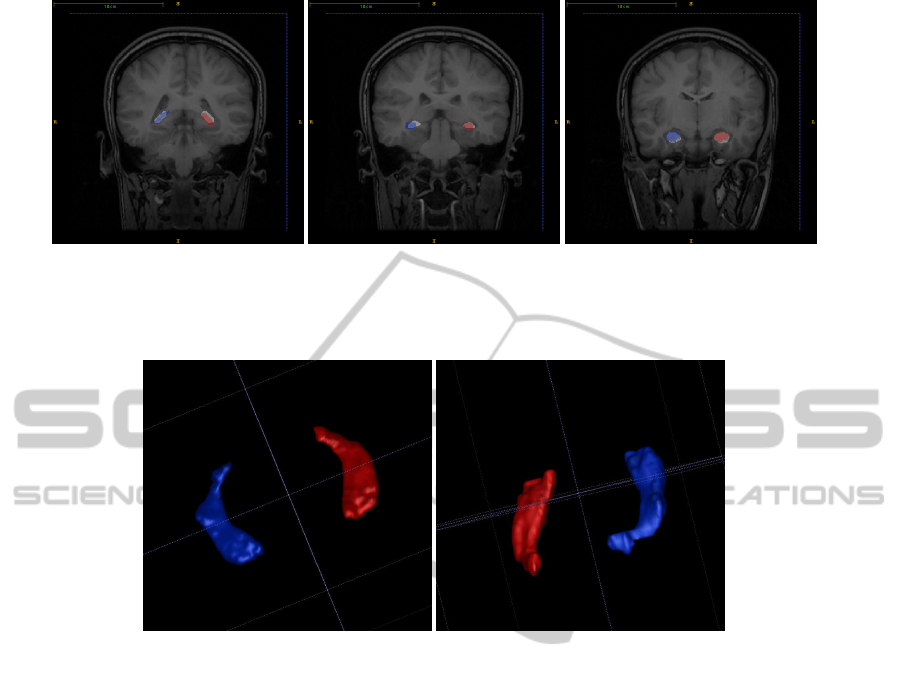

UNSUPERVISED 3D SEGMENTATION OF HIPPOCAMPUS IN BRAIN MR IMAGES